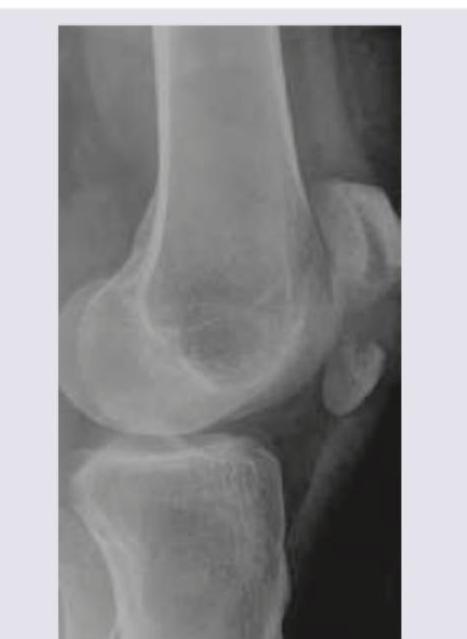

Question 6: Which is the suggested treatment of the lesion shown in the X-ray?

- A. Intramedullary nail

- B. Tension band wiring (Correct Answer)

- C. Patellectomy

- D. Above knee cast

Explanation: ***Tension band wiring*** - The X-ray image shows a **transverse patellar fracture** with some displacement, which is well-suited for tension band wiring. - This technique converts tensile forces on the anterior surface of the patella into compressive forces at the fracture site during knee flexion. *Intramedullary nail* - **Intramedullary nailing** is primarily used for **long bone fractures** (e.g., femur, tibia, humerus) and is not appropriate for patellar fractures. - This method is designed to stabilize diaphyseal or metaphyseal fractures in load-bearing long bones by placing a rod within the medullary canal. *Patellectomy* - **Patellectomy** (surgical removal of the patella) is typically reserved for **severely comminuted** or irreparable patellar fractures, or in cases of infection, which is not indicated by the X-ray. - This procedure can lead to significant functional impairment, including reduced quadriceps strength and increased tibiofemoral joint stress. *Above knee cast* - While an **above-knee cast** can provide - An above-knee cast does not provide **sufficient reduction and compression** for displaced patellar fractures, which are subjected to significant tensile forces. - Conservative management is generally reserved for **non-displaced or minimally displaced** patellar fractures where the extensor mechanism remains intact.